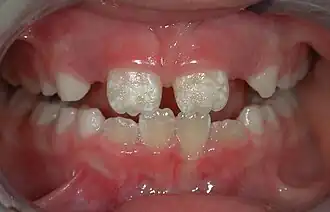

- Pediatric dentistry (also called pedodontics) – dentistry for children

The majority of dental treatments are carried out to prevent or treat the two most common oral diseases, which are dental caries (tooth decay) and periodontal disease (gum disease or pyorrhea). Common treatments involve the restoration of teeth, extraction or surgical removal of teeth, scaling and root planing, endodontic root canal treatment, and cosmetic dentistry.[9]

By nature of their general training, dentists, without specialization, can carry out the majority of dental treatments such as restorative (fillings, crowns, bridges), prosthetic (dentures), endodontic (root canal) therapy, periodontal (gum) therapy, and extraction of teeth, as well as performing examinations, radiographs (x-rays), and diagnosis. Dentists can also prescribe medications used in the field such as antibiotics, sedatives, and any other drugs used in patient management. Depending on their licensing boards, general dentists may be required to complete additional training to perform sedation, dental implants, etc.